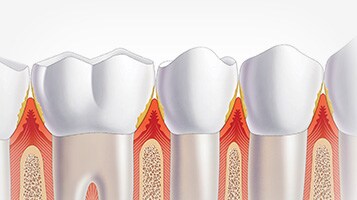

Identifiera en patientbehoven för att se vilka produkter som passar bäst

För olika tandproblem krävs olika och anpassade lösningar. Lär dig om hur Philips Oral Healthcare kan hjälpa dig och dina patienter baserat på de olika tandindikationerna nedan.